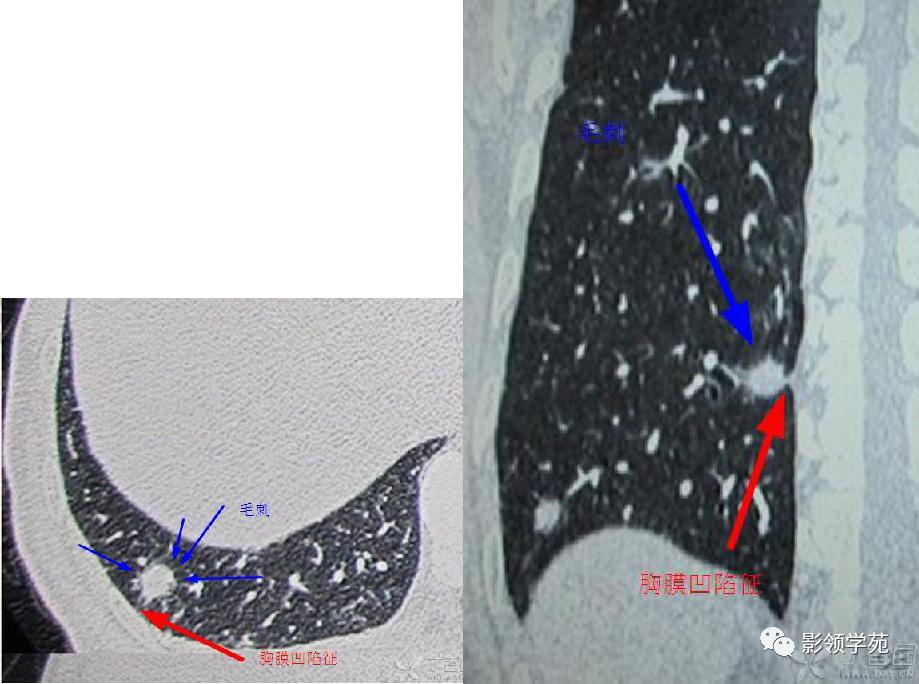

肺内多发结节和肿块是肺Wegener肉芽肿最常见的影像征象,表现为两肺散在分布、多发大小不等类圆形结节或肿块影,以两肺中下野分布多见。部分结节和肿块内可见空洞,洞壁多较厚,内缘光滑或不规则,空洞呈边缘性强化。合并感染时空洞内可形成液-气平面。结节或肿块周围一般都有较短毛刺,部分病灶有长毛刺与邻近的胸膜相连,表现为胸膜凹陷征。这与病理上结节周围存在大量成纤维细胞以及以纤维化形式愈合有关。

-

结节病、变应性肉芽肿、血管炎及脓毒性肺栓塞:多发结节还要与结节病、变应性肉芽肿、血管炎及脓毒性肺栓塞鉴别。结节病临床症状轻,以两肺门纵隔淋巴结肿大为主,变应性肉芽肿和血管炎以一过性浸润性阴影为主。脓毒性肺栓塞不常见,有相关病因,如三尖瓣感染性心内膜炎、外周性脓毒性血栓静脉炎、中心静脉置管感染、Lemierre综合征、肝脓肿、肾周脓肿、牙源性感染、静脉应用**成瘾者、骨髓炎以及免疫机能受损等,两者均可表现为多发的胸膜下结节、楔形影及滋养血管征,但脓毒性肺栓塞的肺结节缺乏毛刺征及胸膜凹陷征。